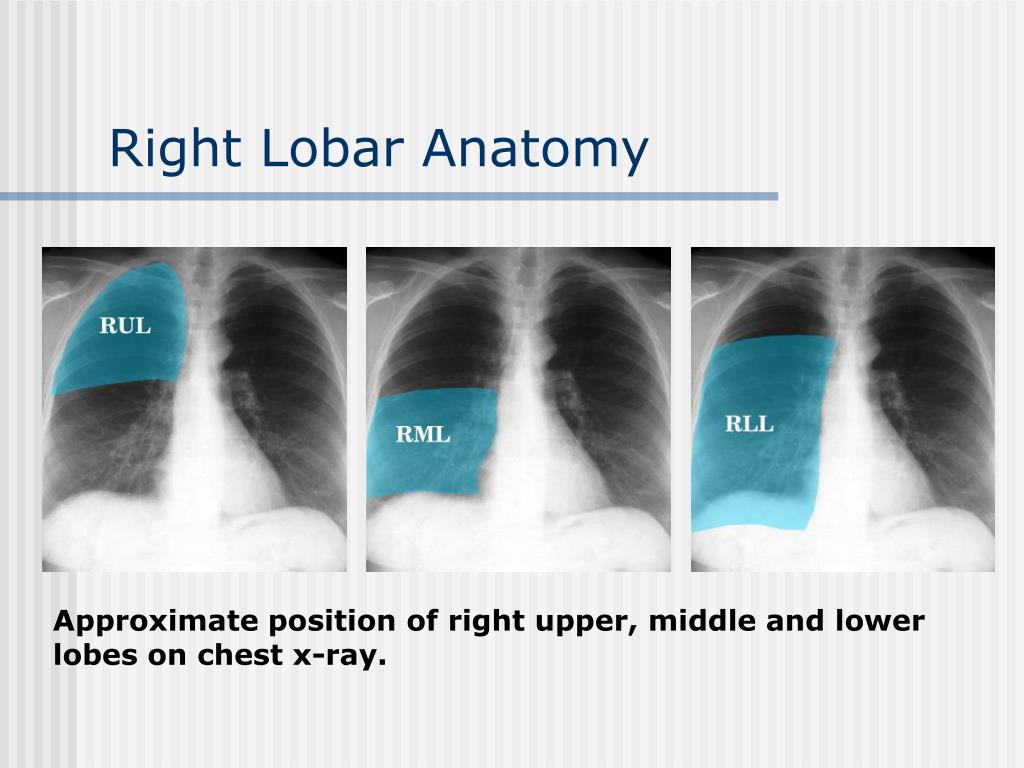

PPT - Chest X-Ray Interpretation for the Internist PowerPoint Presentation - ID:2033573  Holoprosencephaly causes, diagnosis, prognosis and treatment

PPT - Chest X-Ray Interpretation for the Internist PowerPoint Presentation - ID:934924  Lobar cxr anatomy

Lobar cxr anatomy  a Semilobar holoprosencephaly (according to occipitally inclined | Download Scientific Diagram